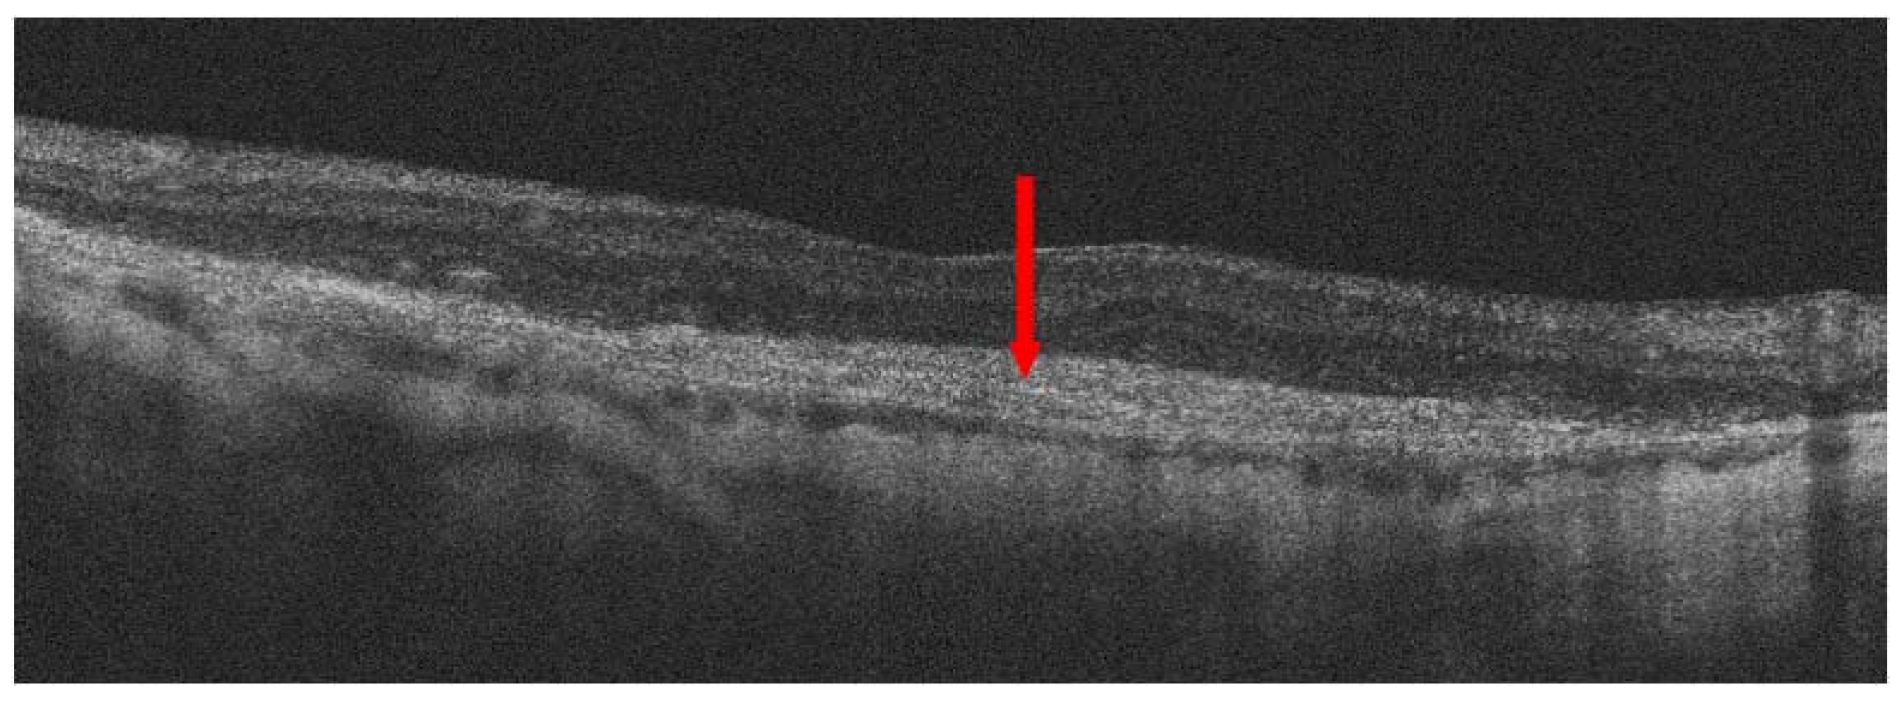

:1. Introduction

3. Treatment of Neovascular AMD